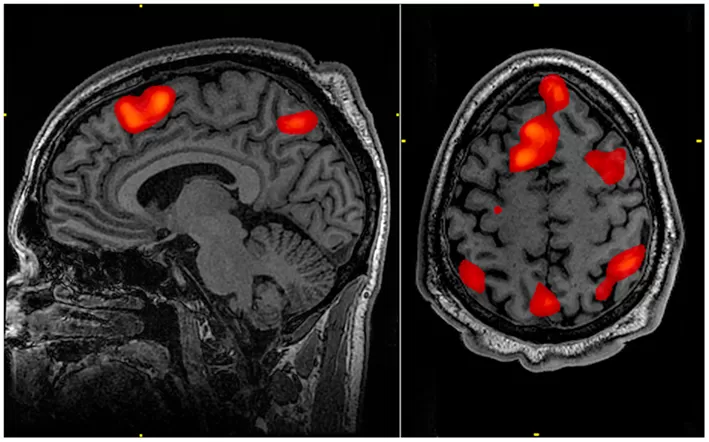

IMAGE 4

An assembly of fMRI images with highlighted regions, used in a public overview article about lie detection and brain imaging.

Visually useful for seeing multiple activation clusters at once, though the field has limits and controversies.